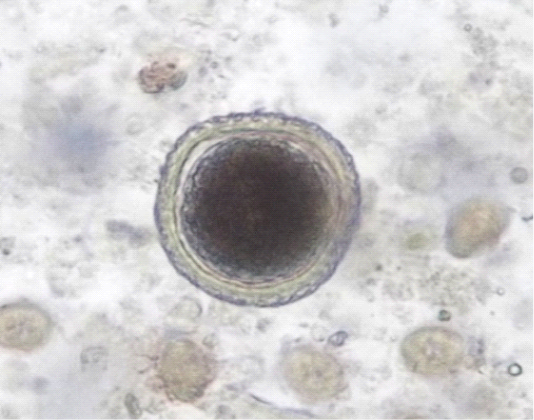

Figure 2

Toxocara vitulorum egg